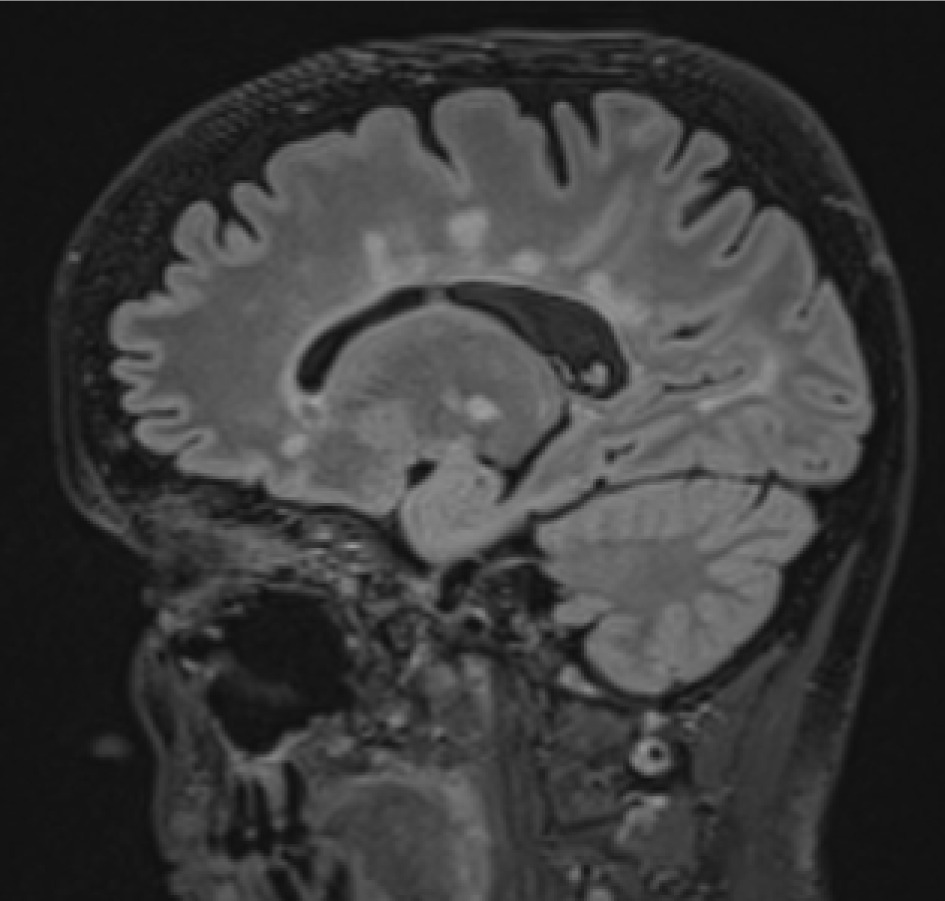

It is important to recognize the enhancement pattern in post gadolinium sequences – typical for MS is open-ring or closed-ring enhancement. Large, multiple closed-ring enhancement indicates other entities like malignancy, acute disseminated encephalomyelitis (ADEM), or infection; if punctuated, we should consider vasculitis or Susac syndrome [4] (Figure 1).